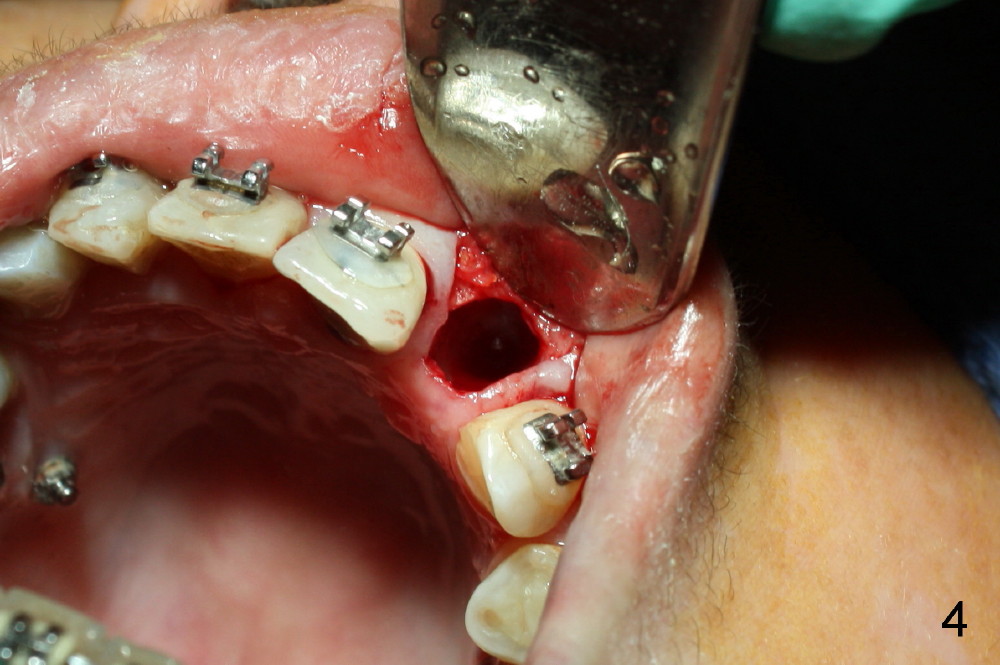

A 56-year-old Oriental lady is going to have immediate implant for the upper left lateral incisor after lengthened preparation (1 2 3 4). There is an indistinct fistula (Fig.1 <) and purulent discharge on anesthetic injection (Fig.2 <). The residual root is exposed (Fig.3 *) following a trapezoidal incision (arrowheads). After tooth extraction and socket debridement with a serrated curette (Fig.4), copious irrigation is conducted with a large monojet and normal saline (Fig.5). The socket will be soaked with non-woven gauze saturated with Clindamycin (Fig.6). The advantage of this antibiotic over Amoxicillin is that there is less mess with the former (completely dissolves). But Clindamycin is bitter. This amalgam well is saved to keep autogenous bone from the reamer and mix with allograft if needed.